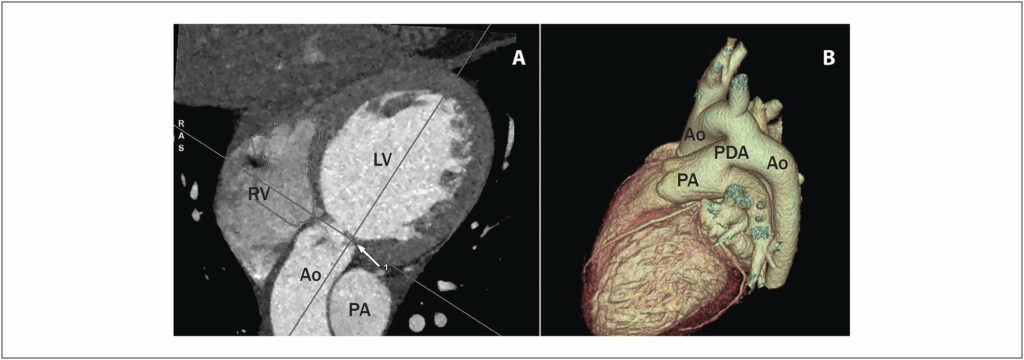

Subaortic Stenosis in Association with Patent Ductus Arteriosus in a Young Woman from the Andes Region

Defects affecting the left ventricular outflow tract (LVOT) are considered major congenital heart defects accounting for 6 out of 10,000 live births. Subaortic stenosis accounts for approximately 1% of all congenital heart defects and 15% to 20% of all LVOT obstruction defects. Subaortic membrane stenosis (SMS) is the most common type of subaortic stenosis, although it is a rare condition scarcely reported in the medical literature., Previous studies have reported its association in some cases with other congenital heart defects such as ventricular septal defects and patent ductus arteriosus (PDA)., Its association with PDA is particularly rare, to the extent that a case series published in 2020 mentioned only 3 previous cases. The objective of this article is to report a case of SMS in association with PDA in a woman from the Andes region.